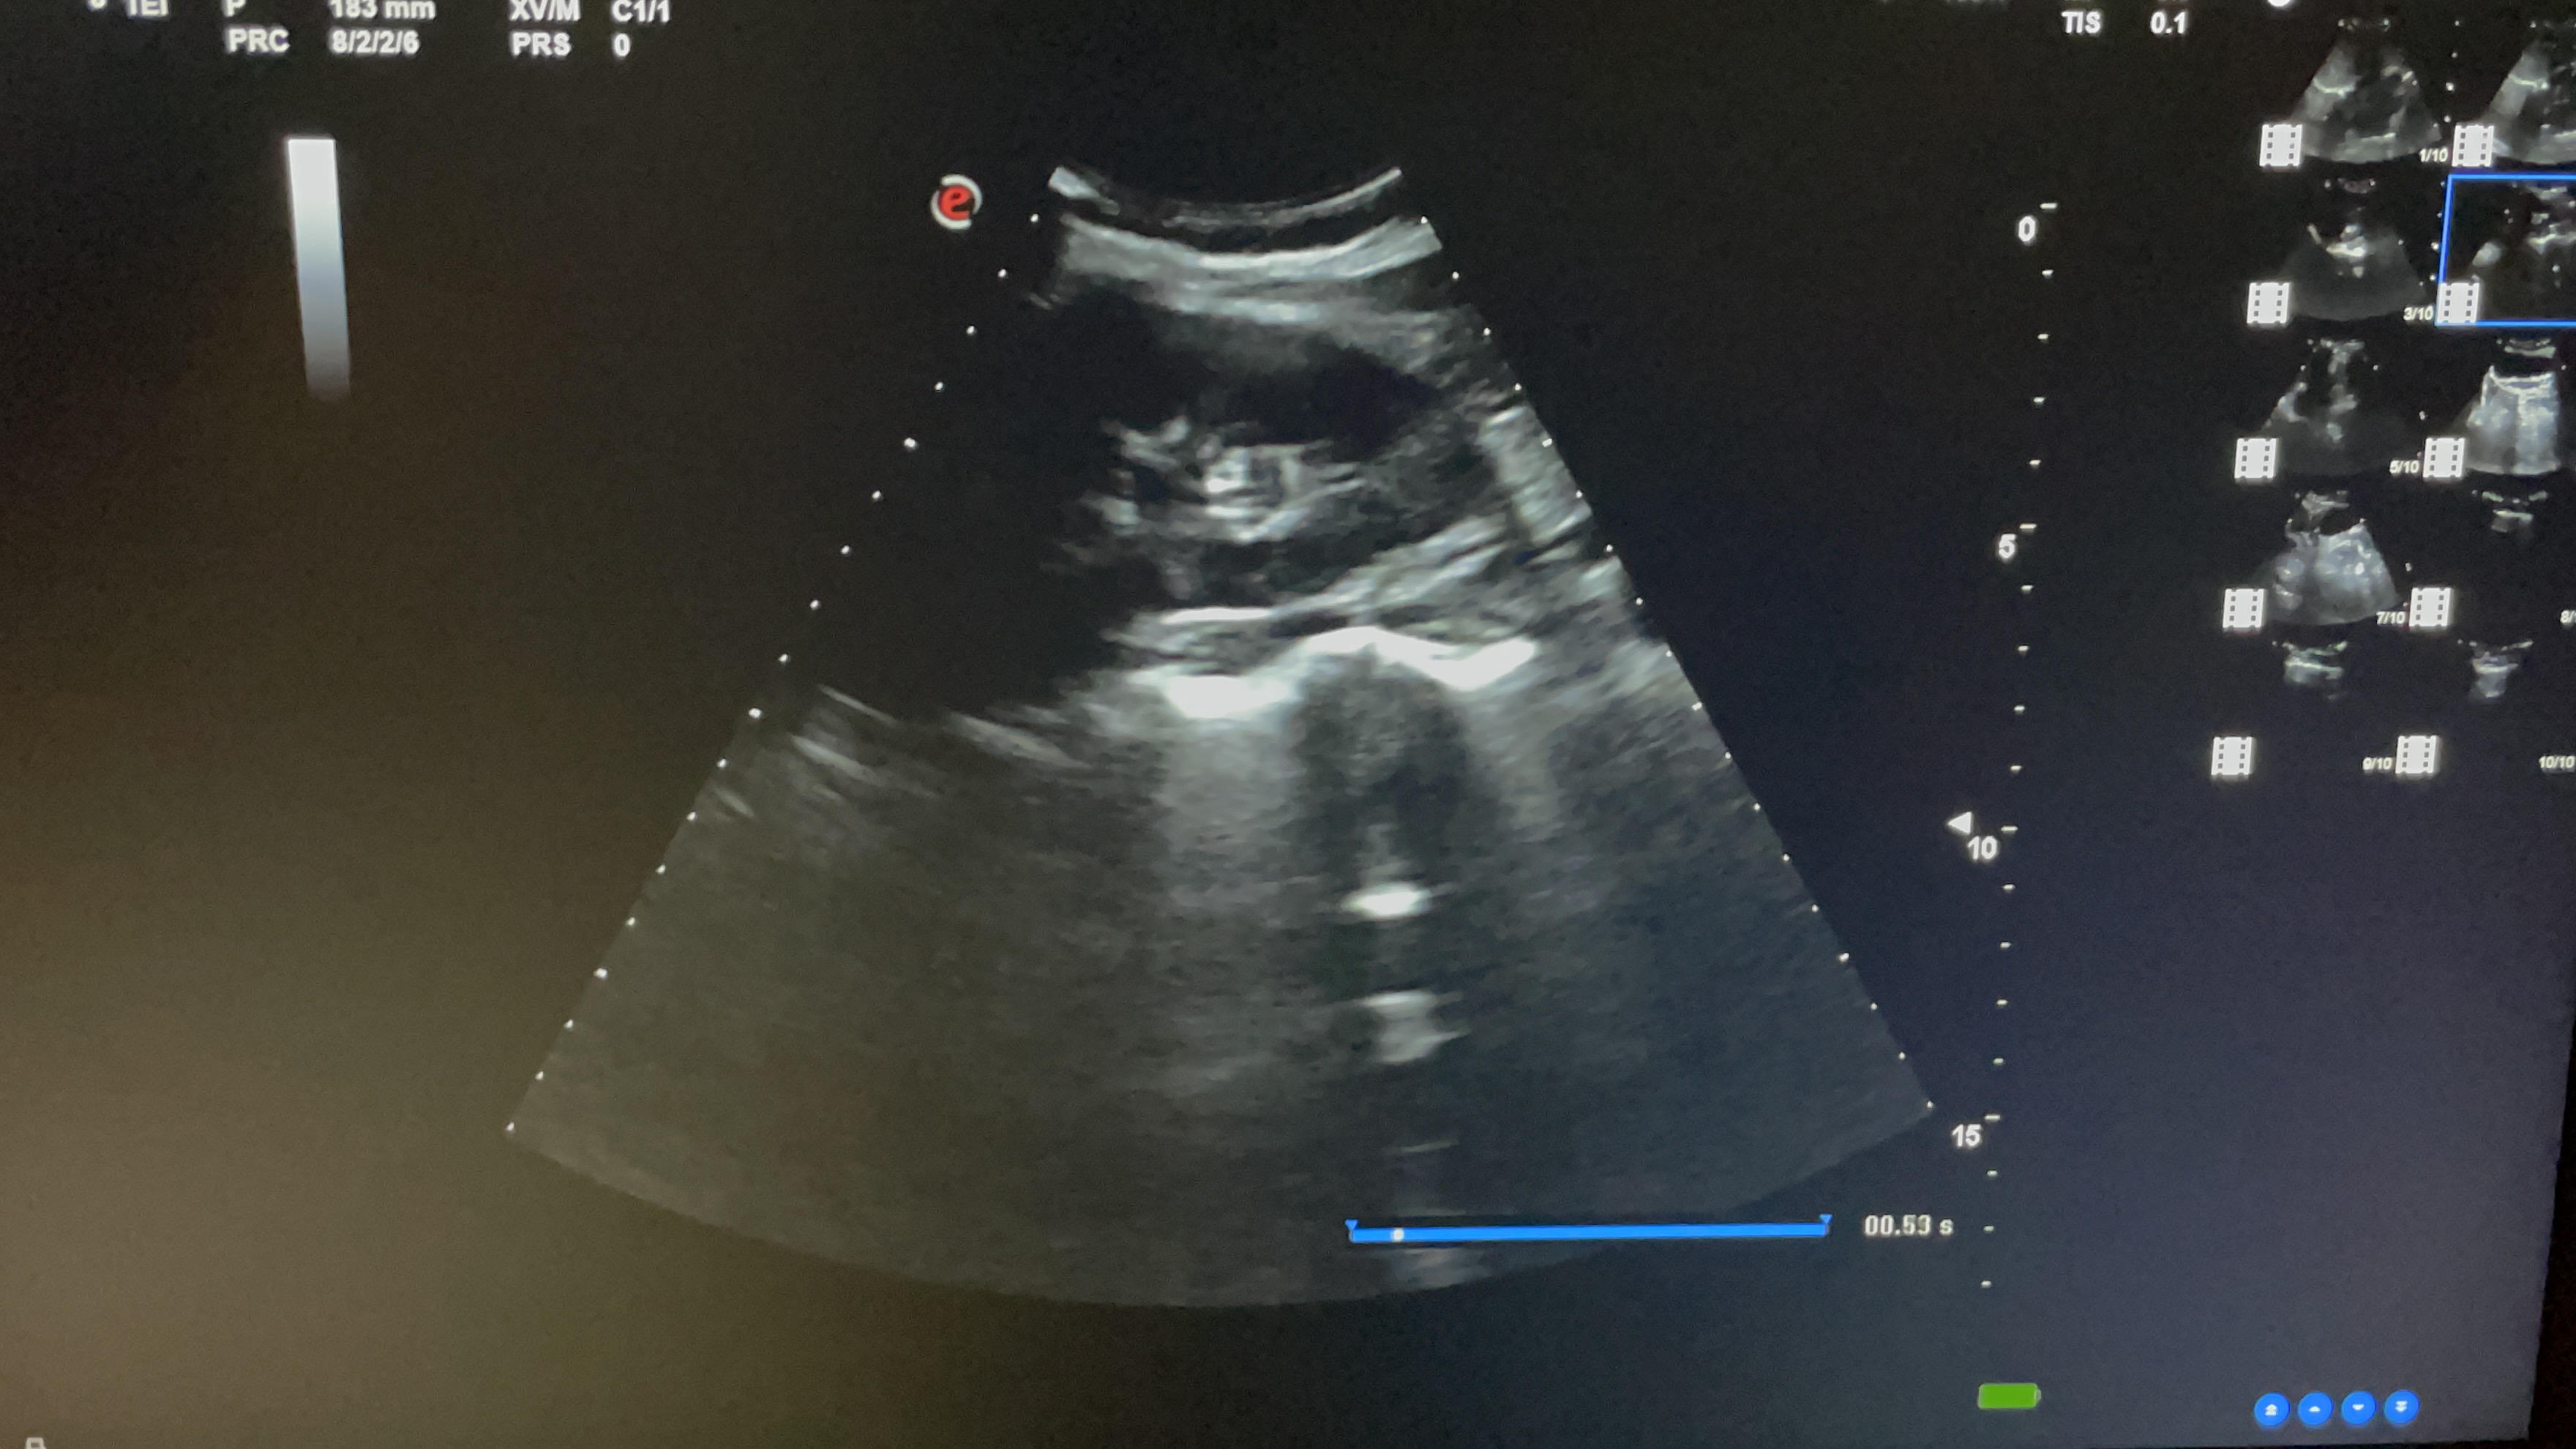

Estudio ecográfico con sonda abdominal de baja frecuencia, siguiendo protocolo ECO-FAST. Se explora región subxifoidea sin apreciarse presencia de líquido en saco pericárdico. Hipocondrio derecho libre de líquido en espacio de Morrison. Hipocondrio izquierdo sin presencia de líquido en espacio esplenorrenal. Imagen de región supra púbica, corte longitudinal y transversal donde no se observa líquido libre en saco de Douglas.